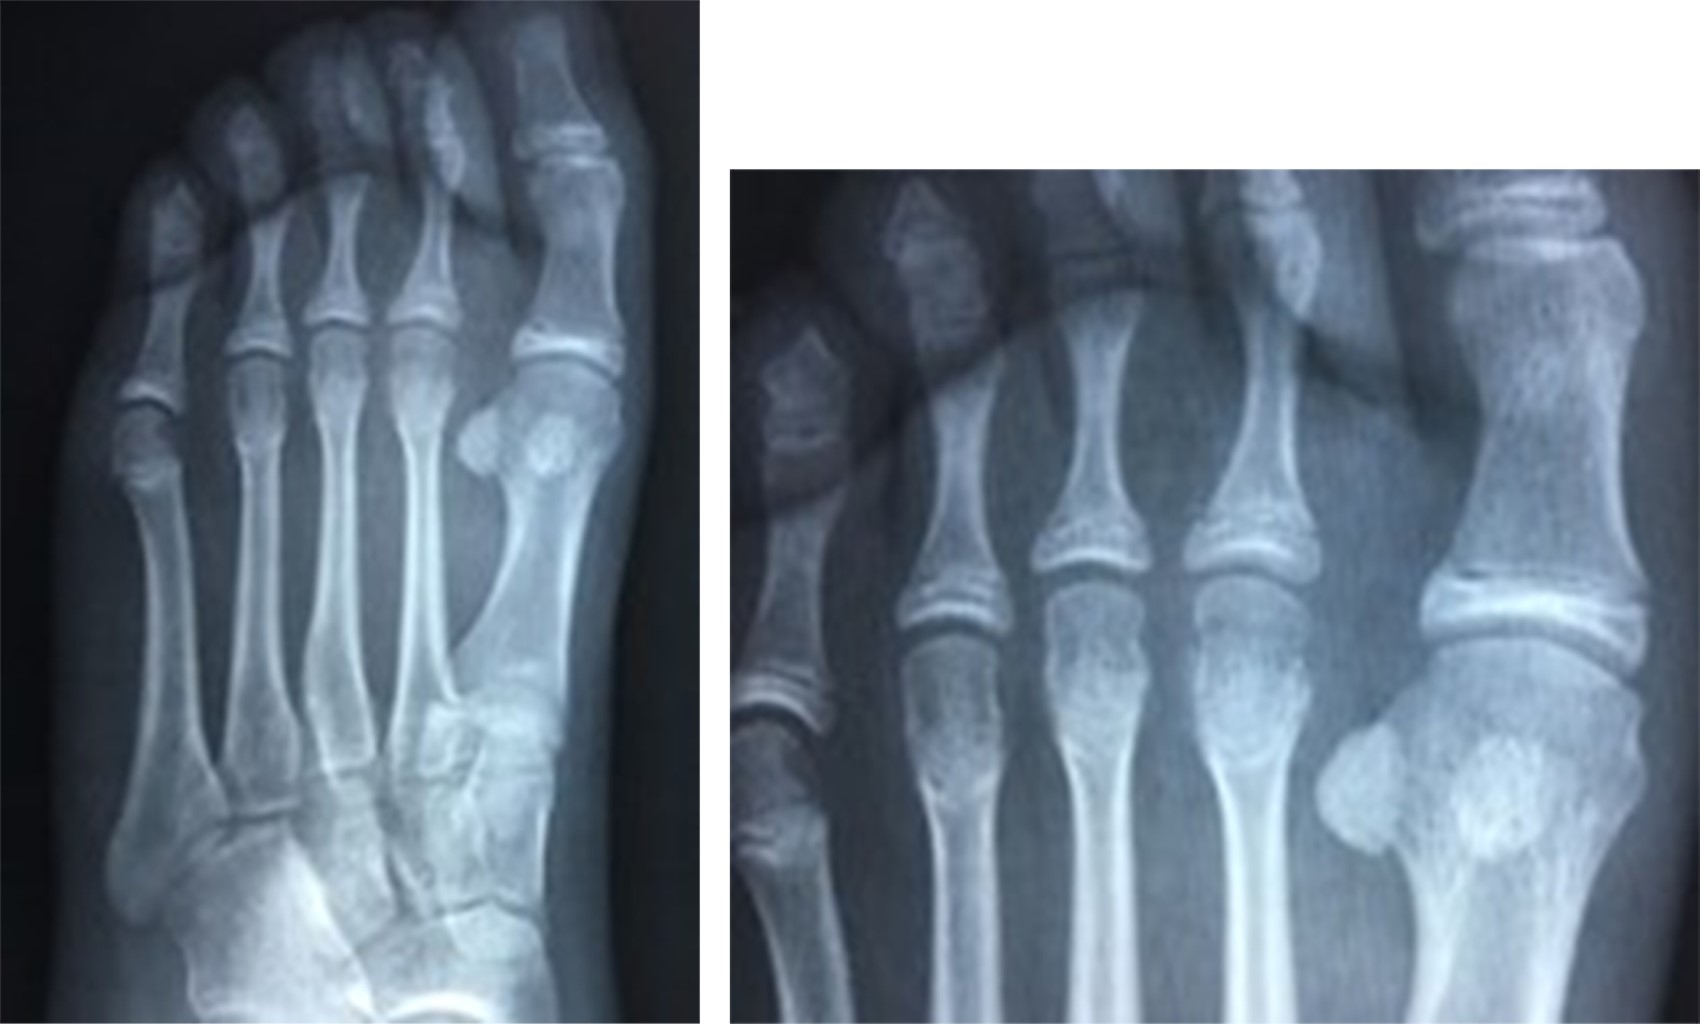

Con previo consentimiento de los padres y la paciente, bajo anestesia local con lidocaína al 2% (3 cm3), se realiza reducción cerrada de la fractura epifisaria mediante tracción del segundo dedo y digitopresión en dirección plantar de la cabeza del metatarsiano. Se toman radiografías de control posterior al procedimiento; se encuentra reducción anatómica de la fractura (Figura 2). Se colocó zapato postquirúrgico por cuatro semanas y se reincorporó a actividades de la vida diaria dos meses posteriores a la fractura. Se realizó seguimiento clínico y radiológico de forma esporádica sin complicaciones en su evolución, se anexa radiografía a 36 meses de evolución (Figura 3).

Caso clínico 2. Masculino de 15 años, sufre contusión directa en dorso del pie derecho al jugar fútbol, posteriormente inicia con dolor y marcha antiálgica, motivo por el cual acude a valoración. A la exploración física llama la atención el acortamiento del segundo dedo, con aumento de volumen y edema en dorso de articulación metatarsofalángica del segundo dedo. Se toman radiografías AP y oblicua de pie (Figura 4); evidencian fractura epifisiaria desplazada de la cabeza del segundo metatarsiano.

Con previo consentimiento de los padres y el paciente, se realiza reducción cerrada bajo anestesia local, se comprueba adecuada reducción con control radiológico (Figura 5). Se coloca zapato postquirúrgico y se inicia marcha a tolerancia. En seguimiento a corto, mediano y largo plazo sin evidencia de complicaciones; se anexan radiografías (Figura 6) a 30 meses de evolución.

Figura 2

Figura 3

Figura 4